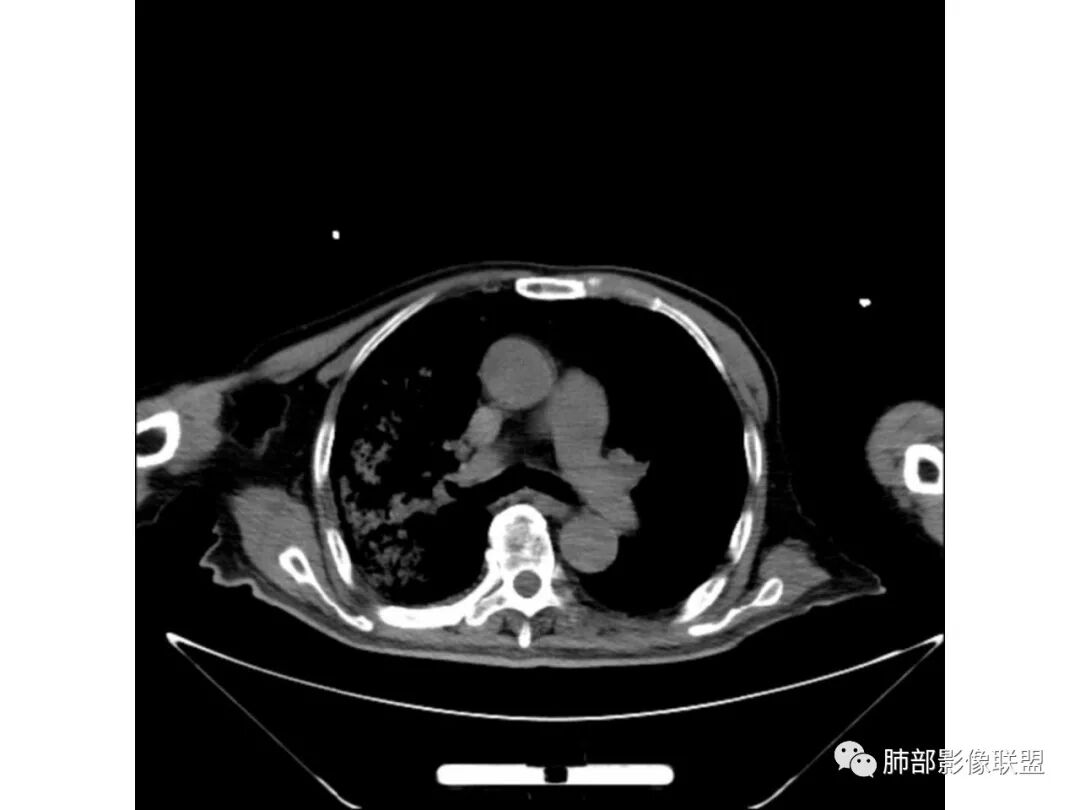

右肺上叶大片实变,其内可见虫蚀样空洞及扩张支气管,其中一空洞内可见曲菌球样结构,右肺体积略缩小。老年糖尿病患者,慢阻肺背景,考虑右肺上叶干酪性肺炎并曲霉感染。

老年糖尿病患者,右肺上叶大片状阴影,内见不规则空洞,内见结节,支气管壁增厚,其他肺野可见气囊影,考虑感染性病变,糖尿病患者常见的四大金刚(金毛结克),金黄色葡萄球菌感染,虽然有气囊,但是临床和其他影像不支持,毛霉菌感染,临床症状重,影像可见液平面,也不支持,肺克临床和影像表现不支持,考虑结核,待排结核合并曲霉菌感染。

老年男性,糖尿病基础,咳嗽,喘咳症状,病程10天,右上肺大片实变,以尖后段为主,实变内空洞影,支气管未见明显扩张,淋巴结肿大,首先考虑干酪性肺炎。但与干酪性肺炎不符的有临床症状轻,实变内支气管扩张不明显,没有树芽征,支气管播散。所以炎性肺癌待排;患者有肺气肿改变,肺气肿合并感染也在考虑范围,但左肺气肿不是十分重,放在第三位。总之,必须结合临床检验,治疗后复查。

右肺上叶大片实变并散在空洞影,洞壁光滑,张力低,部分实变内可见支气管走形,双下肺散在纤维索条及渗出影,纵隔及肺门淋巴结肿大伴钙化,病史有糖尿病,考虑结核,鉴别:肺克,奴卡,毛霉

老年男性,糖尿病患者,右上肺大片实变,内可见多发虫蚀样空洞,右尖段近胸膜处一空洞内可见一类圆形结节影,支气管扩张,淋巴结肿大,双下肺索条,胸膜增厚。结合糖尿病病史,首选考虑结核干酪性肺炎合并曲霉菌感染,待排肺炎型肺癌

老年男性,糖尿病基础,有咳嗽,喘累症状,病程10天,右上肺大片实变,内虫嗜样,无壁空洞,支气管壁增厚,扩张,淋巴结肿大,胸膜增厚,考虑干酪性肺炎,鉴别粘液腺癌。